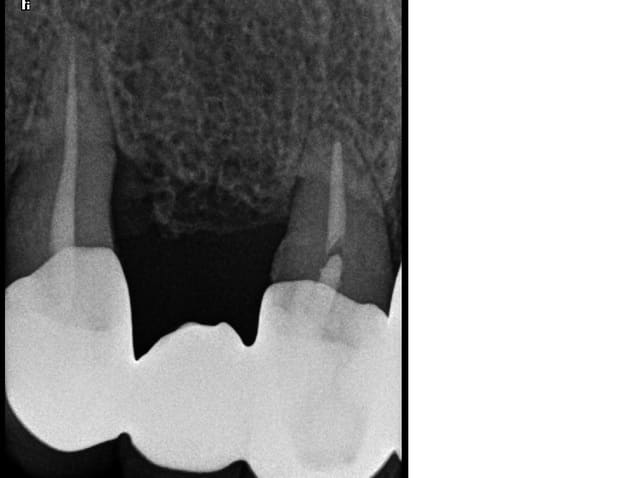

Ra 11 21 22 pn6abq - Eugenol